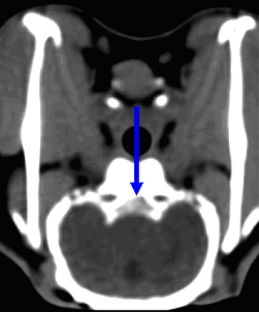

New Zealand White rabbits were randomly assigned to six groups: no SAH/NaCl, no SAH/NO, no SAH/nimodipine, SAH/NaCl, SAH/NO, or SAH/nimodipine. Glyceroltrinitrate (GTN) at 0.5 μg/μl (0.5 μl/h) or nimodipine at 0.2 μg/μl (10 μl/h) or NaCl was continuously infused into the cisterna magna via an Alzet osmotic pump from day 0 to day 5 after injection of 1.0 ml autologous blood. The magnitude of spasm in the basilar artery was determined by comparison of pre- and posttreatment angiography and was calculated as proportional change in intraluminal diameter based on automatic measurements.

A total of 55 experiments and 110 angiograms were performed. SAH was associated with vasoconstriction of the basilar artery (SAH/NaCl group 19.85 ± 2.94%). Continuous intrathecal injection of GTN and nimodipine prevented SAH-induced CVS. There was significant prevention of CVS in animals treated with GTN (SAH/NO group 5.93 ± 5.2%, n = 11) and nimodipine (SAH/nimodipine group: 0.55 ± 2.66%, n = 9). There was no significant difference between the treatment groups and controls in prevention of CVS.